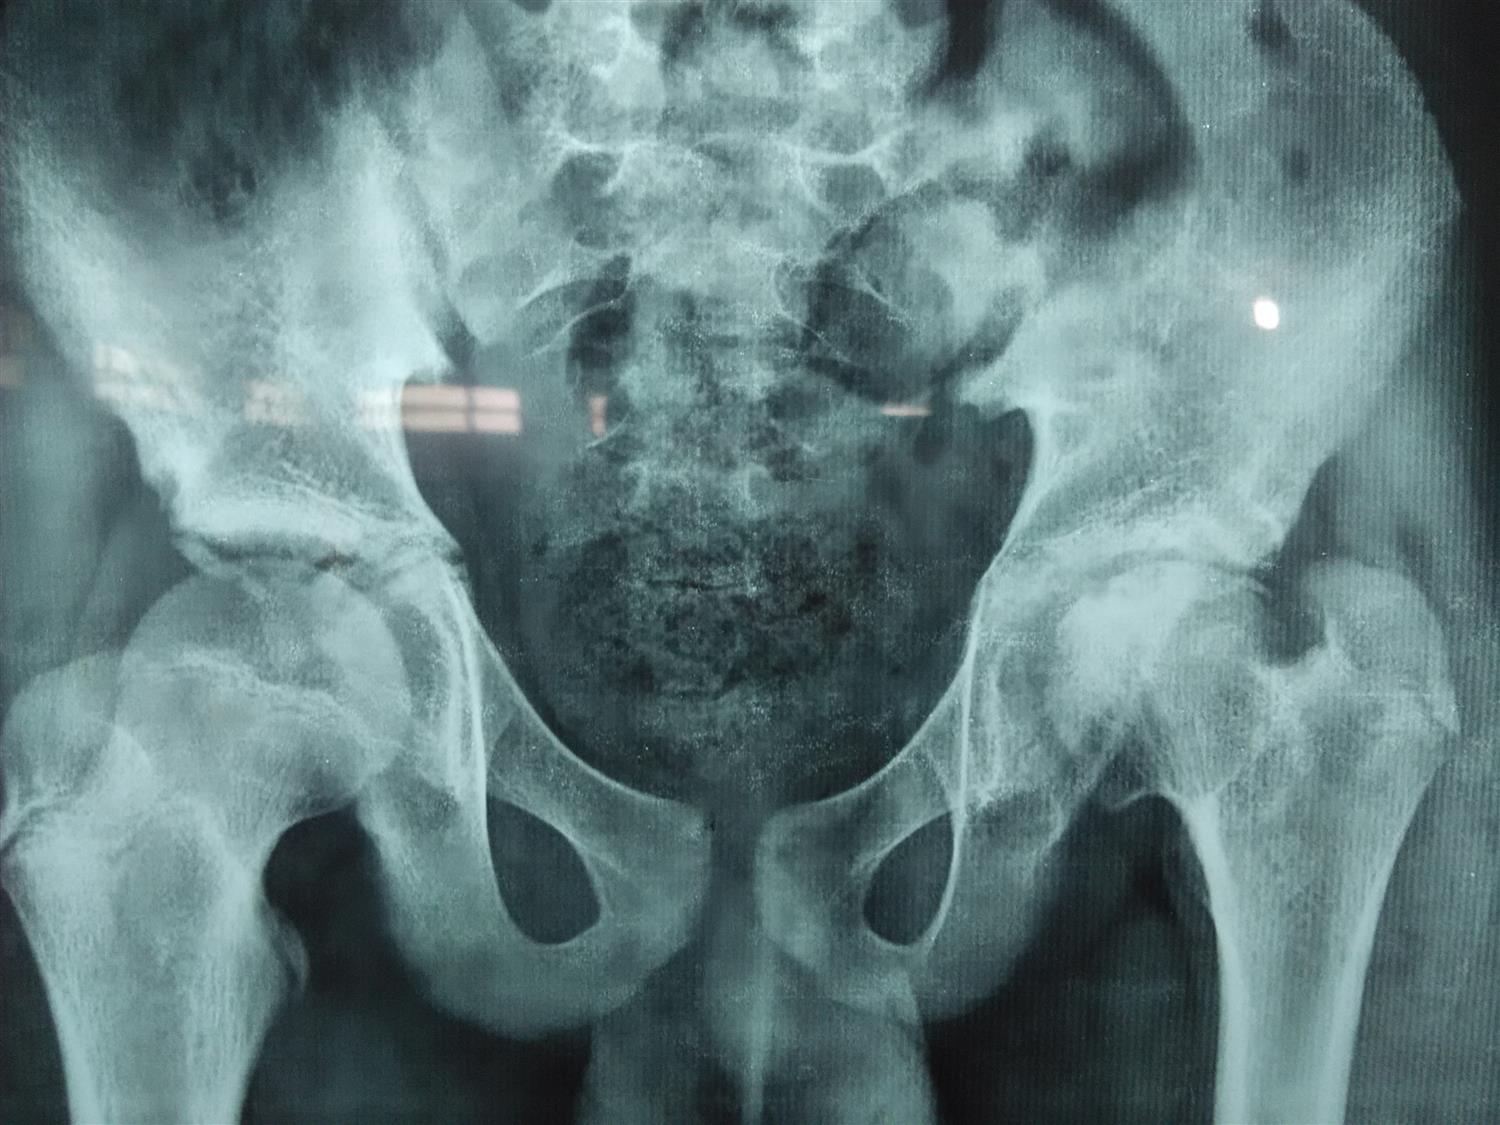

LeggCalvéPerthes disease Image Calves Legg Perthes It is a diagnosis of exclusion and other causes of osteonecrosis (including sickle cell disease, leukaemia, corticosteroid administration, gaucher disease) must be ruled out. It occurs when the blood supply to the head of the femur (thighbone) is disrupted. Treatment is typically observation in children less than 8 years of. It starts when the head of the femur bone (the. Calves Legg Perthes.